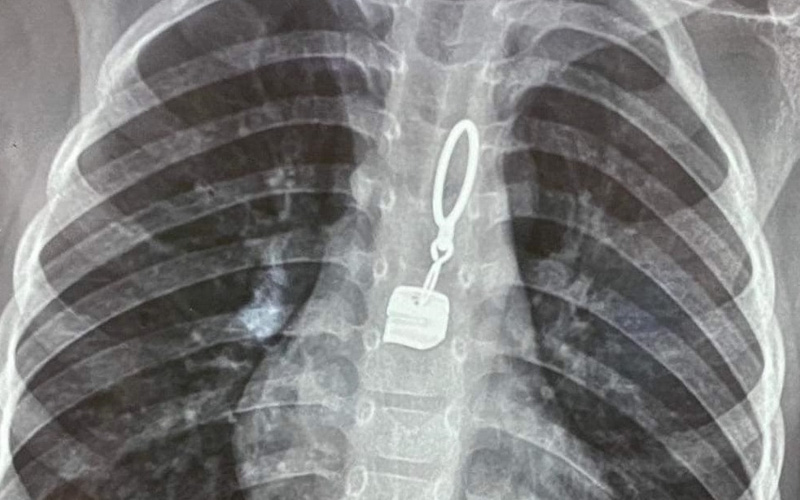

Hình ảnh dị vật trong thực quản bệnh nhi. Ảnh: BVCC

Qua chụp chiếu, các bác sĩ phát hiện trong thực quản của bệnh nhi có dị vật nên đã nhanh chóng chuyển đến Bệnh viện Đa khoa tỉnh Hà Tĩnh.

Khoảng hơn 10 phút, các bác sĩ đã gắp thành công dị vật là một chiếc khóa áo ra khỏi thực quản. Sau khi dị vật được lấy ra, bệnh nhi không còn quấy khóc, đỡ mệt và được chuyển về Khoa Nhi tiếp tục theo dõi.